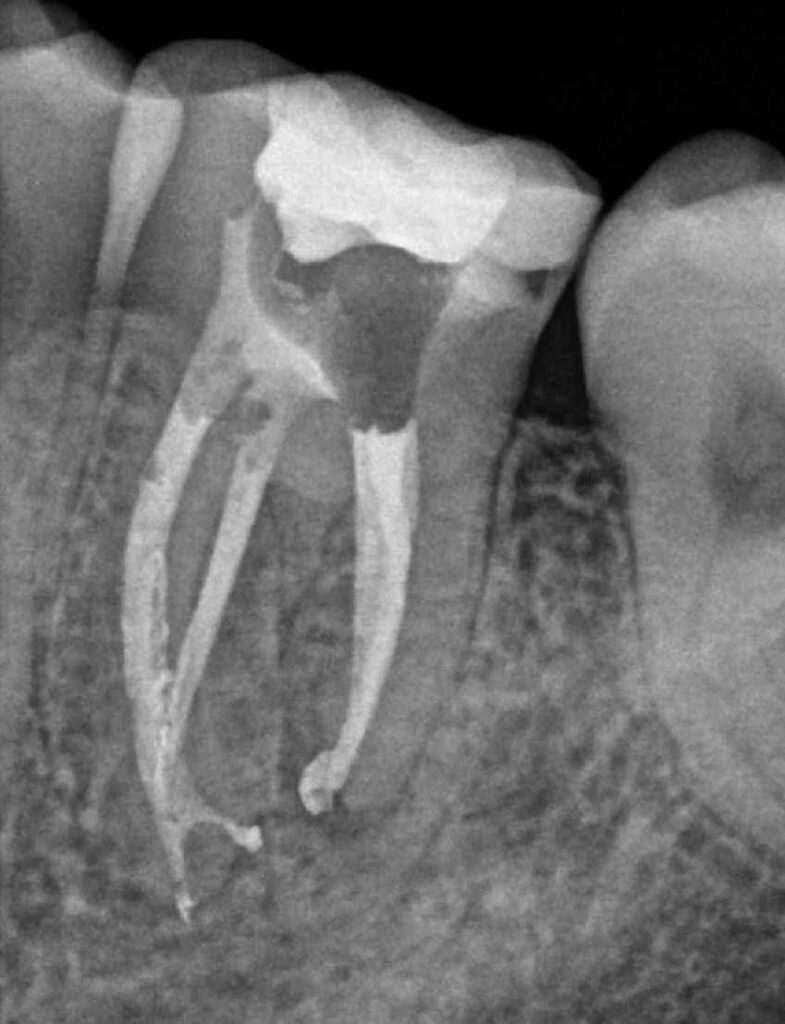

- Mayor precisión: Permite ver detalles minuciosos de los conductos radiculares y estructuras internas.

- Mejor localización de conductos: Facilita encontrar y tratar conductos difíciles de ver.

- Tratamiento más eficaz: Mejora la limpieza y desinfección de los conductos, aumentando las probabilidades de éxito.

- Preservación dental: Minimiza la remoción innecesaria de estructura dental, mejorando el resultado estético y funcional.